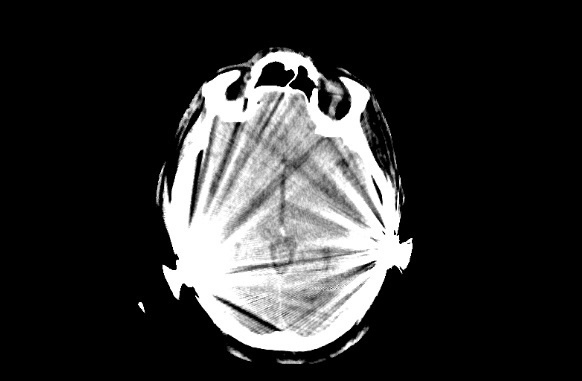

Erschwerend hat der Patient beidseitige Cochlea-Implantate (CI), so dass zum einen ausgeprägte Aufhärtungsartefakte die Diagnostik erschweren (Bild 2 a) und zum anderen eine alternative MRT-Untersuchung nicht möglich ist. In der anschließenden CT-Angiografie, als Spiral-CT gefahren, erschweren die Aufhärtungsartefakte eine genaue Lokalisation des Gefäßverschlusses (CTA Bild 2 b). In dem anschließend sekundär berechneten CTA-Datensatz (Bild 2 c) zeigt sich ein eindeutig zu diagnostizierender Verschluss der rechten A. cerebri media im M2-Segment als Ursache für die linksseitige Hemiparese. Die in der CTA noch ausgeprägten Aufhärtungsartefakte werden nach der SEMAR-Rekonstruktion deutlich reduziert, so dass hieraus auf vergleichbaren Schnittebenen ein klarer diagnostischer Zugewinn resultiert (Vergleich Bild 2 b und Bild 2 c). Zusätzlich kann in diagnostischer Qualität eine Ganzhirnperfusion errechnet werden, so dass die Frage nach einem Perfusionsmismatch ebenfalls beantwortet werden kann.